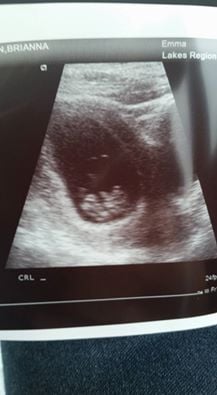

Hi guys, I've already posted my ultrasound, but I have a question that I was wondering if any of you knew the answer to. What is the other black space on the right side? I'm just curious as to what the heck it is haha btw this was an internal ultrasound.